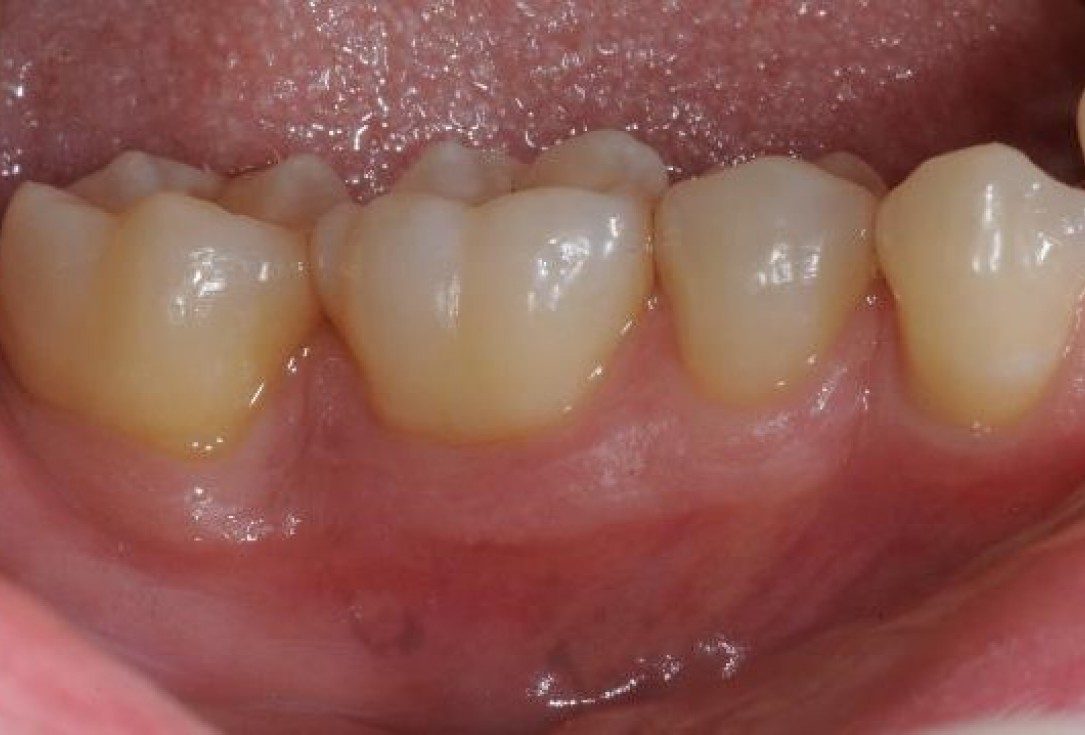

01/22 - Pre-surgical clinical situation, buccal view.

Deep intrabony defects treated using Straumann® Emdogain® - Dr. M. Stefanini